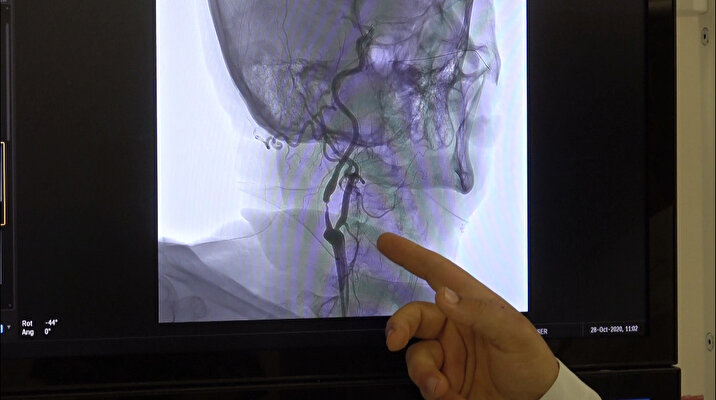

Akciğerleri etkilemesiyle bilinen koronavirüsün, hastalarının 3'te 1'inde ciddi şekilde beyin ve sinir sistemi problemleri yarattığını bildiren Nöroloji Uzmanı Prof. Dr. Zülfikar Arlıer, geçen zamanda elde edilen verilerle bu hastalığın artık en az akciğer kadar beyini de etkilediğinin görüldüğünü vurguladı. Prof. Dr. Arlıer, baş ağrısı, beyinde iltihap, beyin zarlarında iltihap, sinir sisteminde koku- tat duyusunun kaybı, felçlerin tetiklenmesi, denge kaybı, görme kaybı, omurilik etkilenmesine bağlı felçler ve başka birçok nörolojik problemlerin de koronavirüsün kaynağı olduğuna işaret etti.